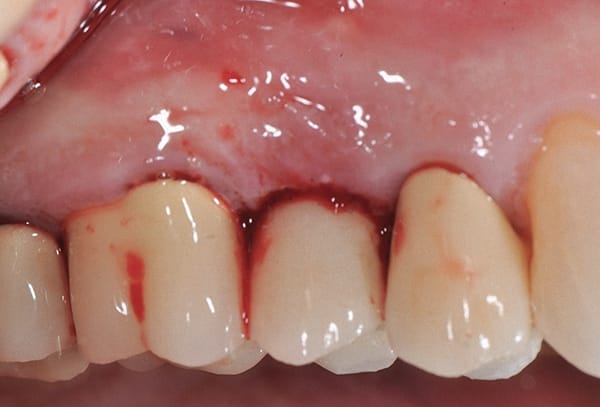

A 63-year-old male patient was referred in 2015 after a routine cleaning at his restorative dentist revealed pocketing and heavy bleeding on probing (BOP) around an implant in site No. 4. The implant (Straumann RN TE) had been placed in 2003 under the author's care due to a previous root fracture of the endodontically treated tooth No. 4, which had been extracted 6 months prior to presentation. The final implant crown was cemented with a polycarboxylate cement in 2003. The patient was highly compliant under his general dentist's care with regular 6-month prophylaxes. In 2015, the patient presented as a healthy non-smoker with a controlled medical history of atrial fibrillation and high cholesterol. Parafunctional habits were contributory to the failed tooth. The patient was diagnosed with site-specific beginning-to-moderate peri-implantitis around No. 4. LAPIP treatment using the PerioLase® MVP-7™ Nd:YAG laser (Millennium Dental Technologies, lanap.com) was performed. At 2 weeks' follow-up, the patient reported 0 out of 10 on a discomfort scale. He maintained good plaque control and returned to his restorative dentist's care after 6 months of healing for alternating periodontal maintenance visits every 3 months. At 7 years' postoperative, the peri-implant tissues associated with No. 4 were healthy with ≤4 mm probing depths and light BOP.